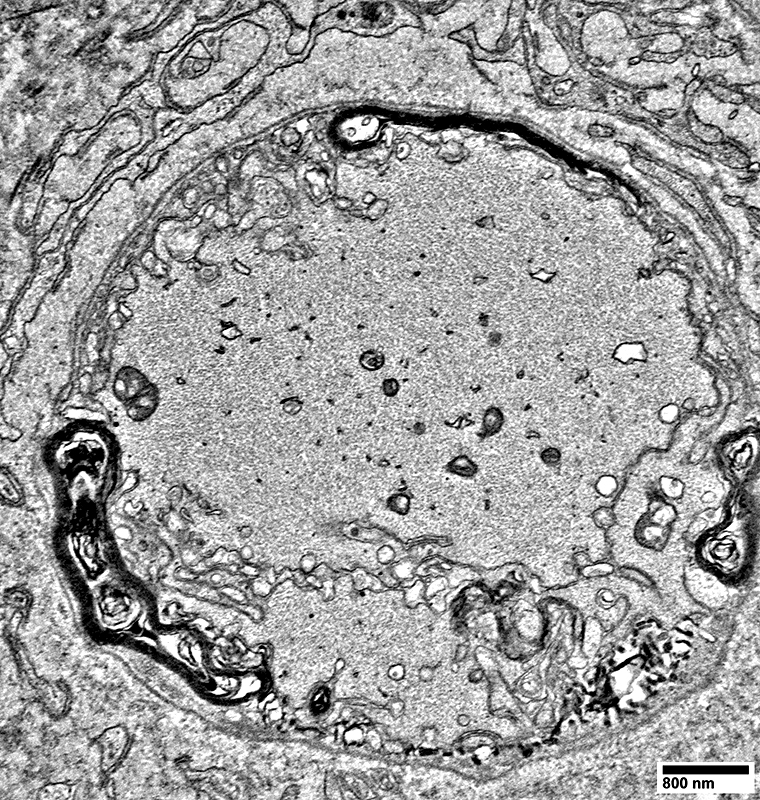

Unmyelinated Axons

Numbers: Relatively preserved; Several per Schwann cell

Non-myeliinating Schwann cells

May have pale cytoplasm (Below)